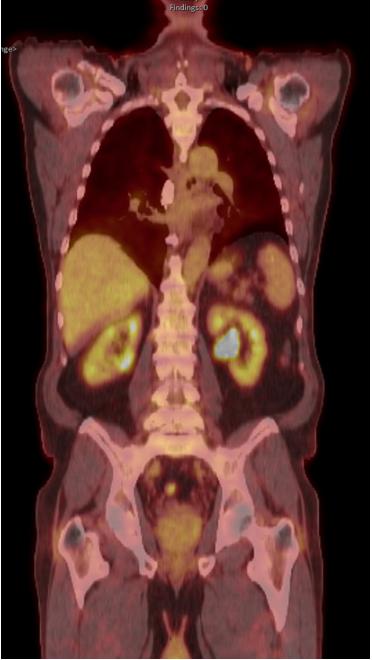

正电子发射断层扫描(PET)显示肾实质内活动均匀,无其他明显的高代谢活动或淋巴结病变(图1)。

图1. 正电子计算机断层扫描图像。在肾实质中均匀活动,没有其他显著的高代谢活动或淋巴结肿大